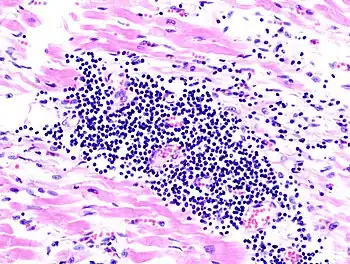

A microscope image of myocarditis at autopsy in a person with acute onset of heart failure

Lymphocytic myocarditis (white arrow points to a lymphocyte), commonly showing myocyte necrosis (black arrow), seen as hypereosinophilic cytoplasm with loss of striations.